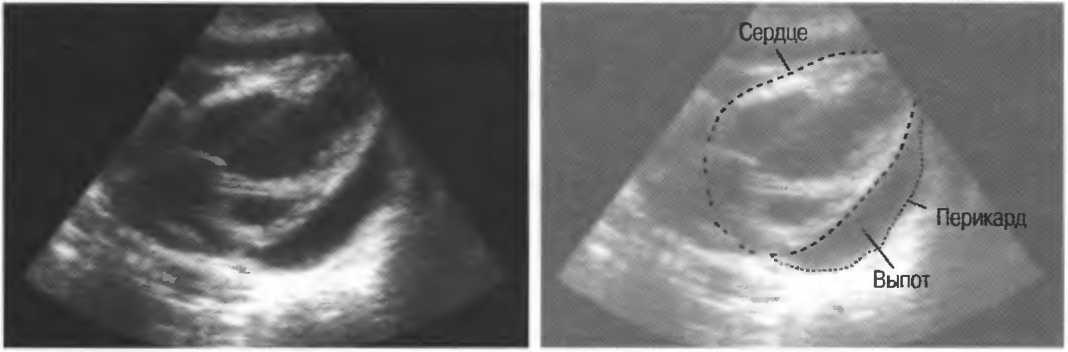

4. Режим дуплексного доплеровского сканирования. Кровеносный сосуд изображается в В-режиме, скорость кровотока определяется доплерографически. Такое сочетание В-режима и доплерографии позволяет более точно получить информацию с данного конкретного сосуда (рис. 2в,г).